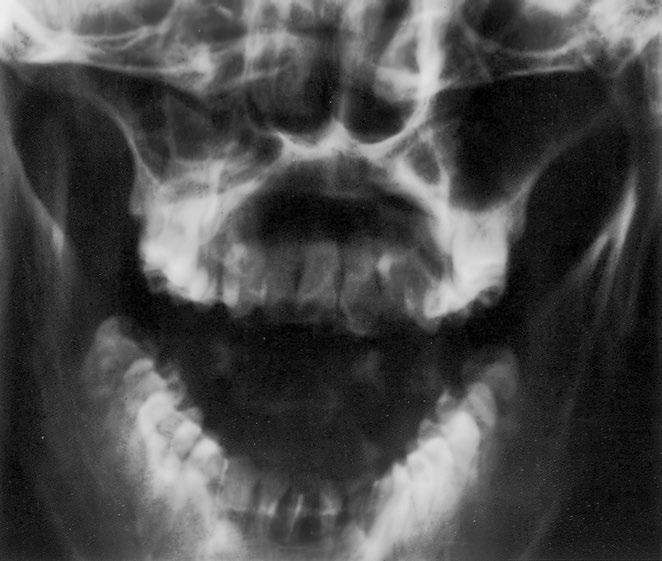

Dolní čelist, Clementschitschova projekce

Dolní čelist je tvarem, velikostí a symetrií normální Pravidelný, stranově shodný tvar a postavení hlavice dolní čelisti Mineralizace a kostní struktura jsou normální Hladké a ostré kontury normálně široké kortikalis Normální kloubní struktury Přiměřený stav chrupu

Zobrazené úseky horní čelisti a obličejového skeletu jsou – lzeli hodnotit –nenápadné

Normální měkké tkáně bez známek otoku, rentgenkontrastních cizích těles či kalcifikací

Závěr

Normální zobrazení dolní čelisti při nenápadném stavu chrupu Normální zobrazení hodnotitelných úseků horní čelisti a obličejového skeletu

Kontrolní seznam

Tvar – dolní čelist (ovál), horní čelist, čelistní dutina, dutina nosní (přepážka uprostřed), lícní kost

– symetrie

– šířka dolní čelisti (hypertrofie, atrofie)

– hlavice dolní čelisti (poloha, postavení: stranově stejné)

Struktura – mineralizace

– spongióza ostře ohraničená

– uspořádání trámců spongiózy normální – bez ohraničených zhutnění, projasnění (např bublinkovitá, případně s okrajovou sklerotizací, linie fraktur)

Kontury – kortikalis hladká a ostrá, šířka na obou stranách stejná – bez ohraničených ztluštění nebo ztenčení

– bez přerušení kontinuity nebo schodovitých deformací

– bez nadzdvižení periostu, resp periostálních apozic

– canalis mandibulae (n alveolaris inferior):

– hladký, bez schodovitých deformací, normálně široký

– hlavice dolní čelisti, resp tuberculum articulare:

– tvar, struktura

– kontura hladká, bez známek destrukce

– kloubní štěrbina normálně široká

– bez kalcifikací nebo cizích těles

Ostatní obličejový skelet

– horní čelist (především ventrální úsek)

– ohraničení dutiny nosní a dutiny čelistní

– os zygomaticum (kost lícní)

– mineralizace

– bez zhutnění, bez projasnění (fraktura?)

Kontury – intaktní, bez přerušení kontinuity, bez schodovitých deformací

– ohraničení hladké a ostré

– bez ohraničených rozšíření nebo ztenčení

Stav chrupu – horní čelist (hodnotitelné jen přední zuby):

– počet, postavení, stav sanace

Měkké tkáně – intaktní, bez otoku, kalcifikací (např slinné žlázy, intraartikulárně či periartikulárně), cizích těles

– dutina čelistní a dutina nosní bez zastínění

Důležité údaje

Stav chrupu (zbývající zuby dolní čelisti): 14 zubů a 2 zuby moudrosti